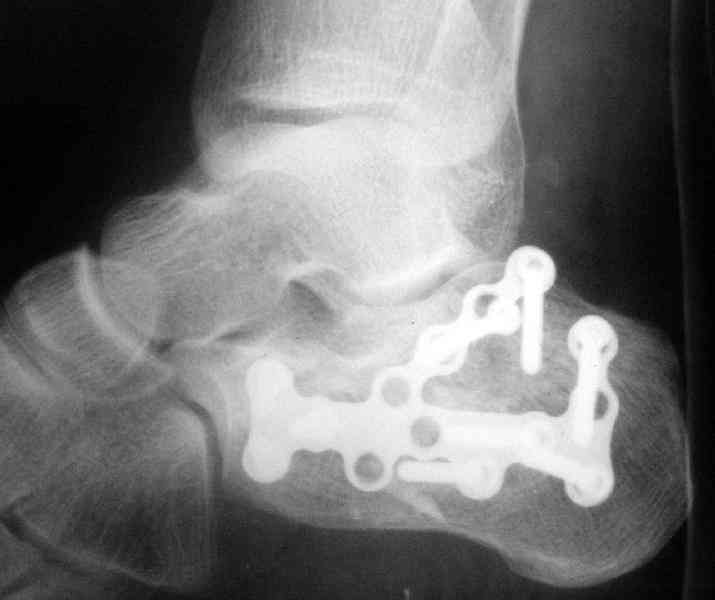

Re: Перелом пяточной кости

Открытый и закрытый способы лечения.